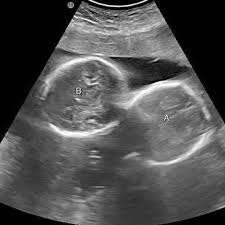

अल्ट्रासाउंड जांच में महिला के गर्भ में दो बच्चों की पुष्टि हुई थी

इंदौर। इंदौर के ESIC अस्पताल से प्रेगनेंसी का एक बेहद चौंकाने वाला मामला सामने आया है. यहां पर एक महिला ने तीन बच्चों को जन्म दिया. इससे भी ज्यादा हैरान कर देने वाली ये है कि जब डॉक्टर ने डिलीवरी से पहले अल्ट्रासाउंड किया था तब रिपोर्ट में दो बच्चे ही दिख रहे थे. लेकिन जब महिला ने तीन बच्चों को जन्म दिया तो डॉक्टर भी हैरान रह गए।

हॉस्पिटल के डॉक्टरों का मानना है कि ऐसे केस मेडिकल फील्ड के रेयर केसेस में से एक होते हैं. महिला ने 1 बेटा और 2 बेटियों को जन्म दिया है. अधिकारी ने बताया कि कर्मचारी राज्य बीमा निगम (ईएसआईसी) के चिकित्सा महाविद्यालय से जुड़े अस्पताल में 27 वर्षीय महिला ने दो लड़कियों और एक लड़के को रविवार (29 मार्च) को सामान्य तरीके से जन्म दिया. इस प्रसव के बाद जच्चा व तीनों नवजात शिशु स्वस्थ हैं।

महाविद्यालय की सहायक प्रोफेसर डॉ. रुचि जोशी ने ‘पीटीआई-भाषा’ को बताया, कि प्रसव के तय समय से पहले पैदा हुए तीनों बच्चों का वजन 1.70 किलोग्राम से 1.90 किलोग्राम के बीच हैं, इनता ही नहीं जन्म के तुरंत बाद से इन बच्चों को विशेष देखभाल प्रदान की जा रही है. उन्होंने आगे बताया कि इंदौर के पास स्थित पीथमपुर औद्योगिक क्षेत्र की रहने वाली महिला दूसरी बार मां बनी है और उसकी एक बेटी पहले से है।

डॉक्टरों का कहना है कि डिलीवरी जोखिम भरा जरूर था लेकिन डॉक्टर की सतरकता ने प्रसव आसानी से हो पाया. डॉक्टर ने आगे बताया कि तीन बच्चों की डिलीवरी थोड़ी कॉम्पलेक्स होती है. साथ ही यहां तो रिपोर्ट और रियलिटी में भी अंतर देखने को मिला है. डॉक्टर ने हिम्मत रखते हुए स्थिति को कंट्रोल किया और मॉनीटर किया. अभी जच्चा बच्चा चारों स्वस्थ हैं।